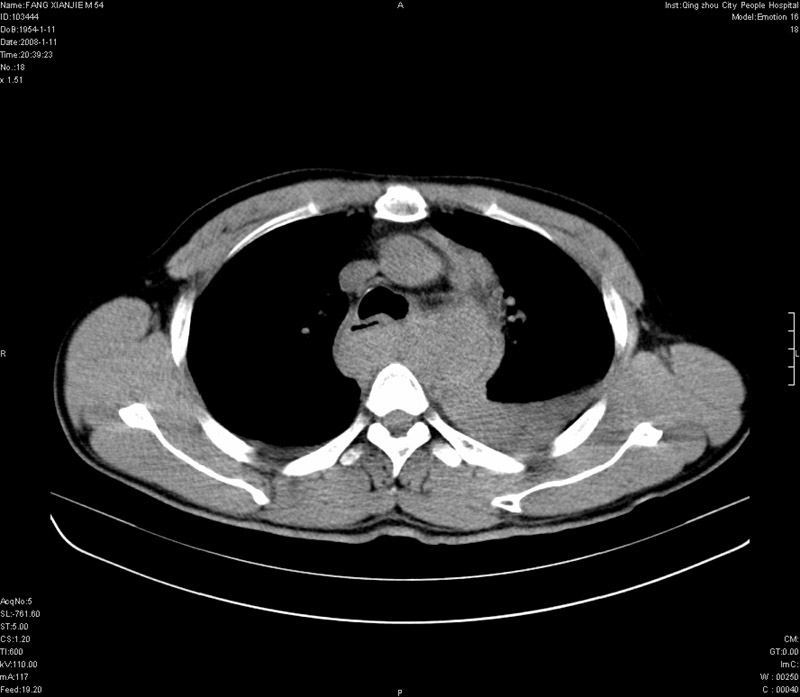

男性,40岁。胸部被车压伤伴胸痛1小时来院就诊。检查:一般情况尚可,血压110/80,胸部及上腹部压痛。结果在三天后公布。骨窗在横断位、冠矢状显示肋骨、胸椎、和胸骨未见骨折征象。

ct11308:胸部外伤1小时(证实病例) (2008-1-13 16:2)结果如下:病人入院后两小时后症状加重,8小时后在征得病人家属同意做了ct增强扫描。如下图。最终临床诊断:外伤性胸主动脉破裂并纵隔内血肿。由于有运动性伪影,胸骨在矢状面重建的图像似有骨折征,这是一种假象,我们称之为“假骨折”,这在多层ct重建中经常性遇到,必要时要结合横断图像鉴别之。现在,病人的一般情况较差,是否要手术家属尚有争议,如果手术修补,难度较大,需要专门预定制作固定支架。

以下是引用拾荒者在2008-1-16 18:46:00的发言:[br]ct11308:胸部外伤1小时(证实病例) (2008-1-13 16:2)结果如下:病人入院后两小时后症状加重,8小时后在征得病人家属同意做了ct增强扫描。如下图。最终临床诊断:外伤性胸主动脉破裂并纵隔内血肿。由于有运动性伪影,胸骨在矢状面重建的图像似有骨折征,这是一种假象,我们称之为“假骨折”,还有双侧肋骨的“假骨折”,这在多层ct重建中经常性遇到,必要时要结合横断图像鉴别之。现在,病人的一般情况较差,是否要手术家属尚有争议,如果手术修补,难度较大,需要专门预定制作固定支架。[br][br]再次表示感谢!

当然,对于该病例,其它非重要的诊断还有:右侧少量气胸;左侧胸腔积液;左侧轻度肺挫裂伤。对于纵隔内血肿,我们曾经遇到过多例,也有怀疑主动脉的破裂,但是,均未得到具体出血部位的明确诊断。